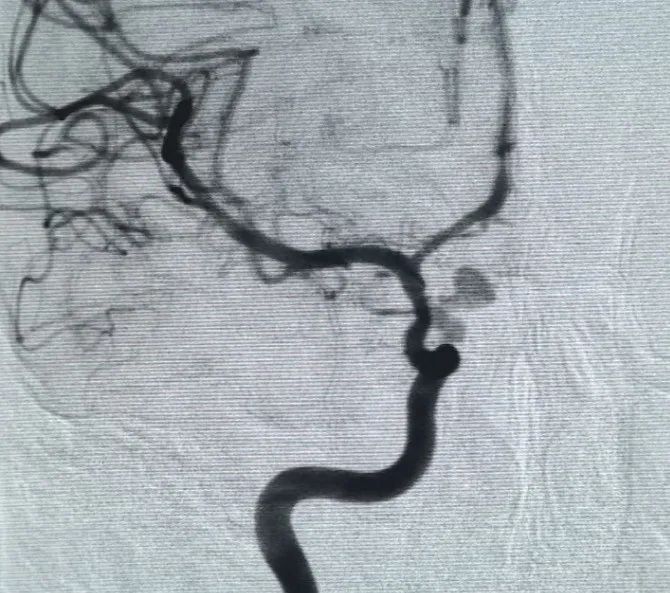

A Perfiller® 3 mm × 6 cm expansible coil and a Perfiller® 3 mm × 2 cm expansible coil were then placed to complete neck occlusion. Subsequently, a Nuva® Flow Diverter (TJED-D-5.0-16) was delivered and deployed across the aneurysm neck. Follow-up angiography in both anteroposterior and lateral views confirmed excellent coverage, good wall apposition, and clear radiopacity, with marked contrast stagnation.

The procedure was completed smoothly with no complications, and the patient recovered without neurological deficits.